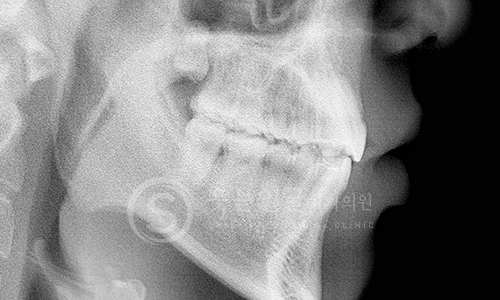

한눈에 보는

임플란트 전후사진